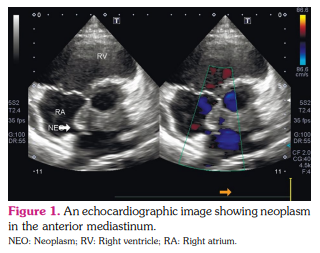

A 25-year-old female patient presented to a rheumatologist with complaints of severe weakness, shortness of breath with mild physical exertion, palpitations, low-grade fever in the evening, tightness of the chest, and weight loss by 6 kg within the past four months. She reported that she felt herself ill for six months. Initial complains were shortness of breath, fever, and pressure pain behind the sternum. The patient consulted a cardiologist, and echocardiography revealed a neoplasm in the anterior mediastinum (Figure 1). The hypodense structure without clear contours, semicircular in the circumference of the non-coronary and left coronary sinus of the aorta, spreading and circularly enveloping the mouth of the left coronary artery, causing a narrowing of the lumen up to 70 to 80% was detected by intravenous contrast-enhanced computed aortography. A similar structure was identified along the pericardial layers in the circumference of the mouth of the pulmonary artery trunk (Figure 2). Due to the impossibility of the radical removal of the neoplasm to clarify the diagnosis, it was decided to perform a biopsy of the mass fragment. Stenting of the left coronary artery was performed. Laboratory test results were as follows: anemia (hemoglobin: 104 g/L); eosinophilia (relative numbers and absolute) 12%, 1.3-1.5x109 /L; erythrocyte sedimentation rate 53 mm/h, and C-reactive protein 31 g/dL. Detected serum immunoglobulin G4 (IgG4) in a high titer-1,030 mg/dL (normal range: 3 to 201 mg/dL). Antineutrophilic cytoplasmic antibodies to myeloperoxidase (ANCA-MPO) were in high titer: 5.2 AI. On multislice computed tomography (MSCT) of the thorax with bolus enhancement, the contrast was accumulated along the periphery and in both lungs with multiple ring-like foci, close to the density of “ground glass” appearance.